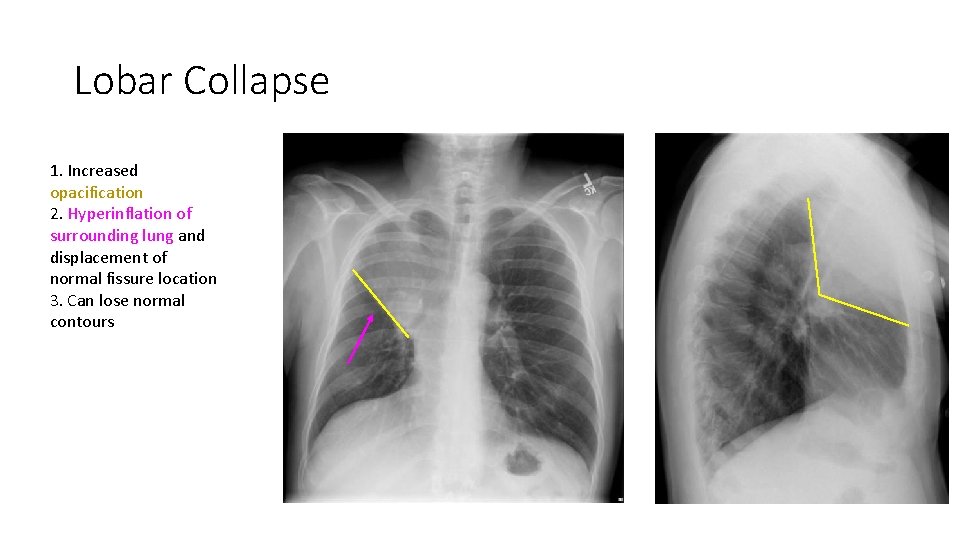

Lobar Collapse 1. Increased opacification 2. Hyperinflation of surrounding lung and displacement of normal fissure location 3. Can lose normal contours